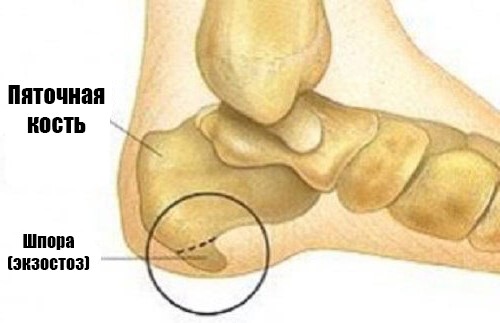

Пяточная шпора (плантарный фасциит) – выглядит как костные наросты в виде шпоры или шипа на подошвенной части стопы. При передвижении шип давит на окружающие ткани провоцируя развитие болевого синдрома. В среднем размеры шпоры обычно составляют 0,5-1,2 см. В медицине такой нарост называют – экзостоз.

По статистике в большинстве случаев (около 90%) происходит изменение походки в силу того, что человек подсознательно пытается уменьшить неприятные болевые ощущения вызванные давлением шипа. В итоге при ходьбе человек пытается скомпенсировать движения и больше напоминает движение лыжника. Для точного определения необходим рентген и обследование с помощью аппарата УЗИ, а также анализы крови и мочи. Целью этого является не только постановка правильного диагноза, но и выяснение причины вызвавшей развитие болезни.